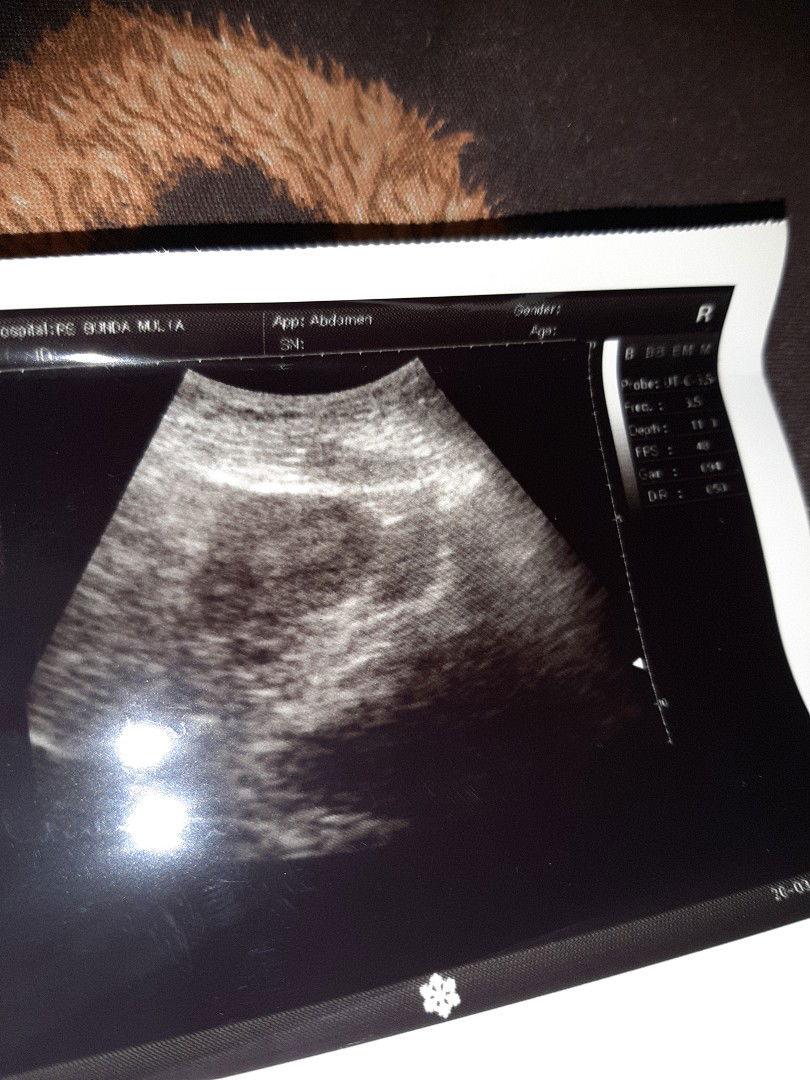

Siapa bunda" disini yg punya pengalaman usg penebalan didnding rahim saat telat haid dan hasil test pack negatif tp hasilnya hamil

Test pack negatif Telat 15 hari USG

Saya sudah USG bun krn telat 15 hari TP masih negatif ternyata ada penebalan dinding rahim Ada yg pernh ngalamin atau pengalaman yg sama akhirnya hamil atau haid bun

Saya pernah bun, sudah 3 bulan telat mens di USG ternyata ada penebalan dinding rahim, dan seminggu setelah USG saya haid